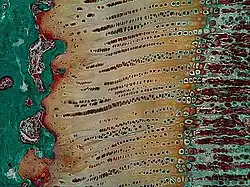

Light micrograph of an undecalcified epiphyseal plate that is displaying the hypertrophic zone with its typical chondrocytes, matrix and three zones: maturation (top), degenerative (middle) and provisional calcification (bottom). | |

The growth plate has a very specific morphology in having a zonal arrangement as follows:[8]

| Epiphyseal plate zone (from epiphysis to diaphysis) | Description |

| Zone of reserve | Quiescent chondrocytes are found at the epiphyseal end |

| Zone of proliferation | Chondrocytes undergo rapid mitosis under influence of growth hormone |

| Zone of maturation and hypertrophy | Chondrocytes stop mitosis, and begin to hypertrophy by accumulating glycogen, lipids, and alkaline phosphatase |

| Zone of calcification | Chondrocytes undergo apoptosis. Cartilagenous matrix begins to calcify. |

| Zone of ossification | Osteoclasts and osteoblasts from the diaphyseal side break down the calcified cartilage and replace with mineralized bone tissue. |